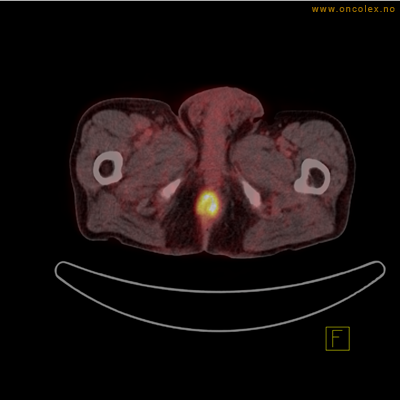

Vev som tar opp mer radioaktivt stoff, synes som hvite områder som lyser opp mer i forhold til annet vev som tar opp mindre sukker.

Høyt opptak av 18F-FDG ved analkreft.

Høyt opptak av 18F-FDG i adenokarsinom i rektosigmoideumovergangen. Fysiologisk opptak i blæren.